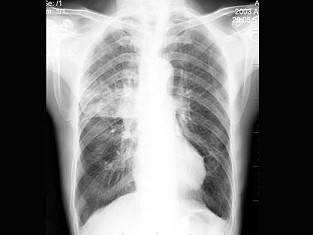

E.大血管

女,45岁,寒战、高热1周,WBC:1.8×109/L,胸片如图,应首先考虑()